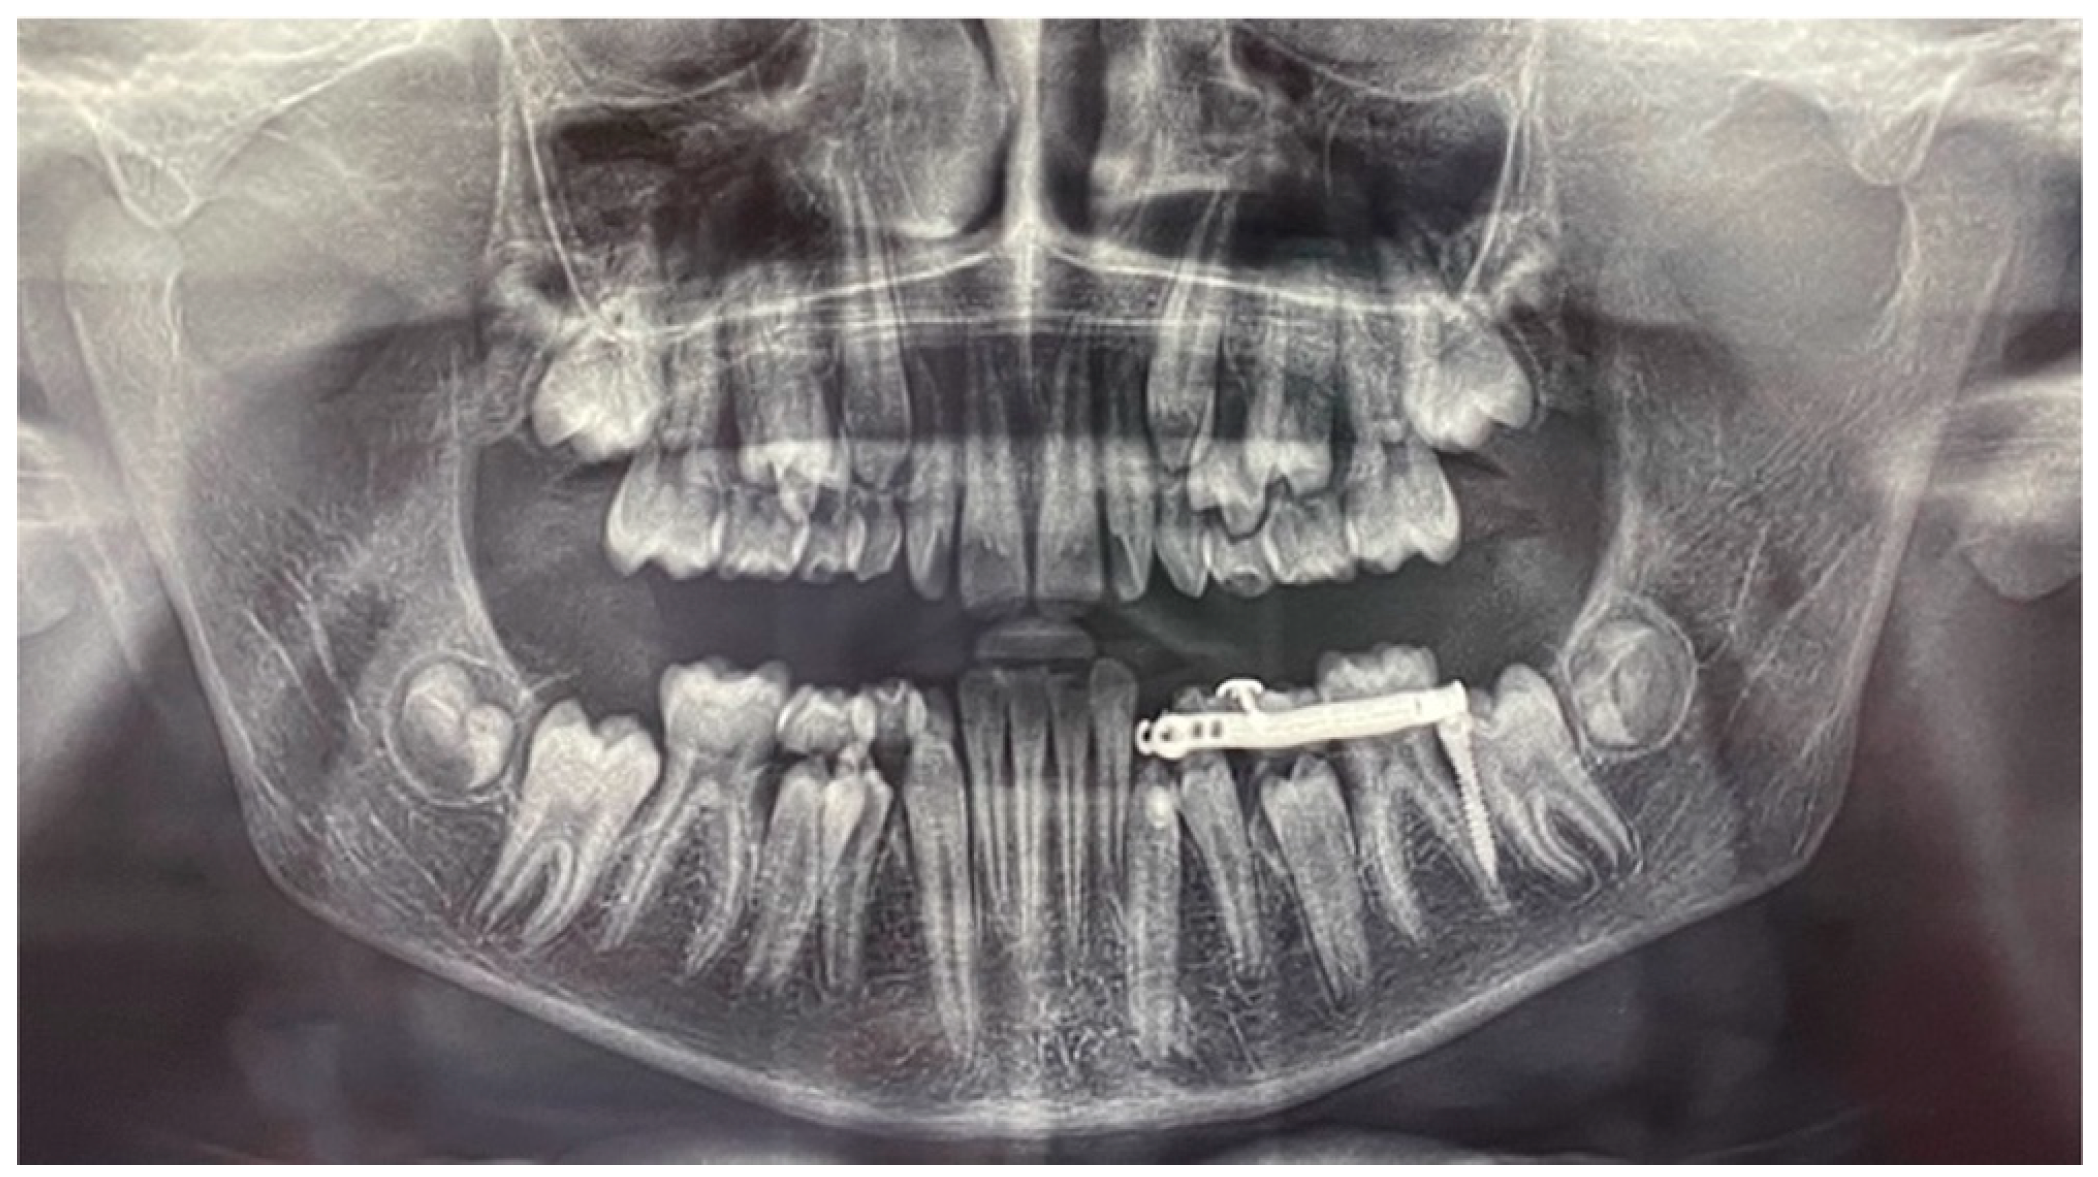

A panoramic radiograph showed that element 3.3 was deviated from its normal eruption path. The cuspid of the impacted canine was tilted mesially and positioned at the level of the right central incisor (element 3.1), close to the lower third of the root. The angle of the long axis of the canine to the line passing through the midline, traced according to Bertl et al. [4], was 60°. The deciduous element 7.3 was still present with its entire root (Figure 3).

Figure 3. Pre-treatment panoramic radiograph. The angle subtended by the line passing through the mandibular midline (red) and the line passing through the long axis of the mandibular canine (black) were traced.